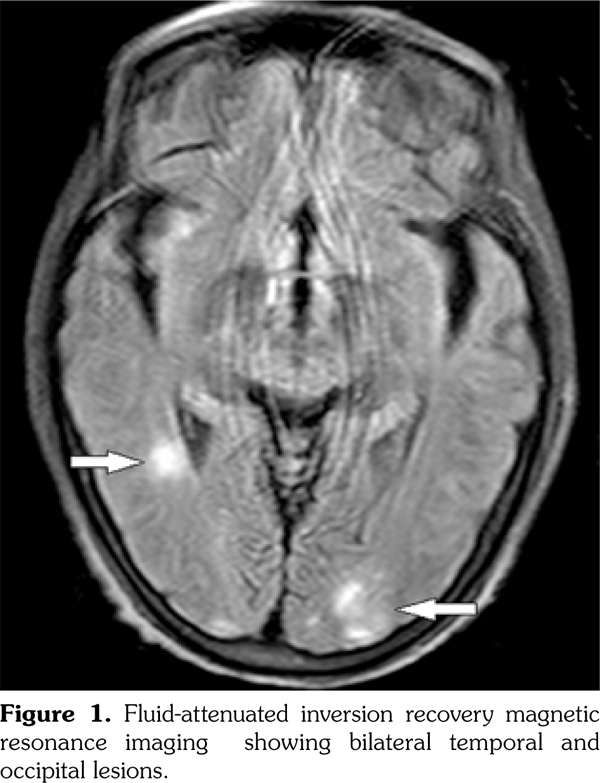

Posterior reversible encephalopathy syndrome (PRES) is known as reversible posterior leukoencephalopathy syndrome, primarily portrayed in 1996.(1) It is characterized by headache, vomiting, seizure, confusion, and visual disturbance. The brain magnetic resonance imaging is the diagnostic gold standard showing edema in the white matter of bilateral temporal, parietal, and occipital lobes for neuroradiologic characteristics, totally reversible.(2) To our knowledge, this is the first report of an elderly female patient of PRES complicated with systemic lupus erythematosus (SLE), Sjögren syndrome (SS), and primary biliary cirrhosis (PBC).

A 65-year-old female patient was admitted because of upper extremity shaking and lower extremity weakness for one day, fatigue, and anorexia for more than two months. She was firstly suspected of Parkinsonian syndrome. Levodopa and benserazide hydrochloride tablets were administered. However, her condition deteriorated aggressively, and it was hard for her to walk. Meanwhile, there were no complaints of rash, oral ulcer, baldness, arthritis, or photosensitivity. She denied headache, dizziness, vomiting, confusion, or double vision. Interestingly, she suffered from dry mouth and dry eyes for several months. She had never smoked or consumed alcohol, or received any suspected drugs. Physical examination was significant for fractured teeth and decreased myodynamia with 4/5 strength of upper extremity and 2/5 strength of lower extremity symmetrically. Laboratory tests revealed elevation of the 24-hour urine protein (1.20 g), positive autoantibodies (antinuclear antibody, anti- Smith, anti-double stranded deoxyribonucleic acid antibody) and decreased complement. SLE was diagnosed.(3) The positive tests of anti-Sjögren syndrome A antibody and Schirmer test, ocular staining score (>3) combined with clinical symptoms supported the diagnosis of SS,(4) but the patient refused labial salivary gland biopsy. Furthermore, PBC was diagnosed according to her raised alkaline phosphatase and positive serum anti-mitochondrial antibodies, excluding other causes of cholestasis. However, she rejected liver biopsy. Magnetic resonance imaging of the brain revealed symmetrically patchy lesion involving predominantly the subcortical white matter of the bilateral temporal and occipital (Figure 1). Therefore, she was ultimately diagnosed with PRES, SLE, SS, and PBC. Treatment was initiated immediately, including methylprednisolone 80 mg once a day, cyclophosphamide 400 mg∞3 days, plasmapheresis, and hypotensor. Several days later, her clinical symptoms improved greatly. Repeated magnetic resonance imaging was performed two months later, showing that the lesion had almost disappeared. Urinary protein proved to be 0.06 g/24 hour in follow-up. A written informed consent was obtained from the patient.

Compared to SS and PBC, PRES in SLE patients is relatively frequent. Younger age is independently associated with PRES episodes in patients with SLE and the mean±standard deviation age (years) is 27.9±1.1.(5) However, our patient was older. Besides, the lesion was different from conventional lupus encephalopathy, which frequently occurs in frontal lobe and parietal lobe. The underlying pathophysiology of PRES complicated with autoimmune diseases are as follows: theories including dysfunction of autoregulatory cerebral perfusion mechanisms and endothelia, inflammasome activation of interleukin-18 and neutrophil extracellular trap formation and the presence of autoantibodies (N-methyl-D-aspartate receptor and anti- aquaporin 4) were studied.(6-9) Recent genome- wide studies have pointed out that risk loci, such as interferon regulatory factor 5-transportin-3 may be associated with the genetic susceptibility to both SLE and PBC.(10) Osteopontin, recognized as one of the spontaneous autoimmune models of SLE, may also be related.(11) Although the majority of patients have active disease and are on immunosuppressive therapy prior to developing PRES, they still require an increase or continuation of their immunosuppressive therapy to control disease activity after the onset of PRES.